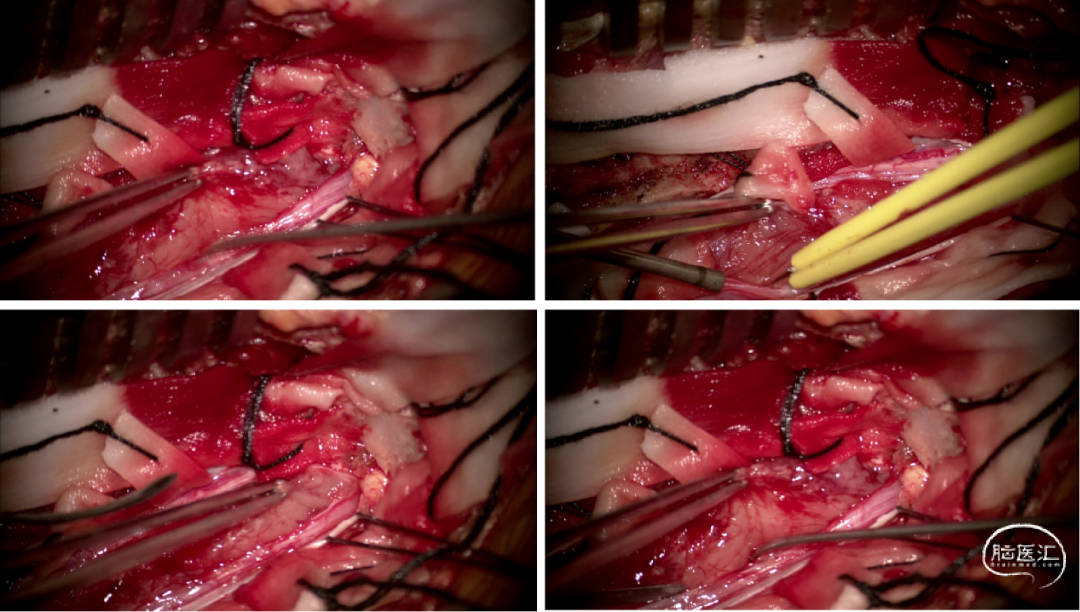

手术情况

硬脊膜张力高,脊髓向背侧膨出,与脊髓腹侧粘连紧密,肿瘤挤压脊髓,肿瘤边界分离,减少对胸髓的牵拉,降低了术后患者神经功能发生的概率,术后患者肢体麻木症状改善。